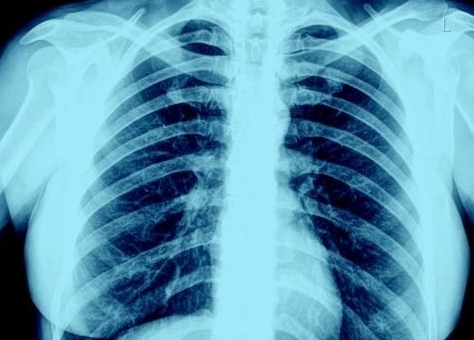

텍사스 공대 소속의 외과 전문의인 브리트니 뱅크헤드-켄들 박사는 "그동안 엑스레이 촬영 결과 코로나19 환자의 폐에서 짙은 상흔이 발견되지 않은 적이 드물었고, 애연가들과 비교해 상태가 더 나빴다"고 밝혔다.

폐 상태가 안 좋을수록 엑스레이상에서 흰색 부분이 많이 나온다.

정상적인 폐는 대개 검은색인데, 이는 공기가 많이 들어가 있는 건강한 상태를 의미한다.

반면 애연가의 폐는 상흔과 충혈 때문에 흰색 부위가 곳곳에서 나타나며, 코로나19 환자의 경우 폐 전체가 거의 흰색으로 나왔다고 그는 설명했다.

또 무증상 감염자라고 해도 엑스레이 촬영 결과 폐에서 심한 상흔이 발견되는 비율은 70∼80%에 달한다고 그는 덧붙였다.